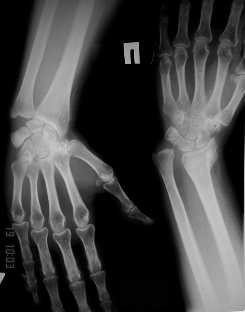

Уважаемые коллеги! Обратилась женщина, 55 лет. Травма 3 месяца назад, лечилась по месту жительства (Рис.1). Косорукость, боли, ограничение движений.

Досняли - рис.2-6. Хотелось-бы услышать мнения об объеме операции. С уважением, Юрий Алексеевич Булахтинглавный травматолог Камчатского Военно-морского госпиталя

u pazientki po nauchnomu ulna abutment/impingment syndrome posle posttraumaticheskogo ukorochenia radiusa

na rengene znachitelnoe ukorochenie radiusa, sustavnaia poverchnost naklonena dorsalno chresmerno , chetko vidno nekongruentnost DRUJ - distalnogo radioulnarnogo sustava ,ulna prosto vtikaetsia v triquetrum .

Да, действительно, в наличии так называемый посттравматический ulnar impaction syndrome. Есть несколько вариантов лечения этой патологии-данного случая. Вполне можно выбрать вариант и предложенной выше тактики. А кто-то даже после остеотомии лучевой кости наложит аппарат внешней фиксации и одновременно устранит дорсальную ангуляцию и удлинит лучевую кость. Можно предусмотреть и другие варианты. Если не очень расстраивает дорсальная ангуляция, то при отсутствии артроза в области дистального радиоульнарного сочленения ( а пока такого, по-видимому, нет)и нестабильности этого сустава можно просто укоротить локтевую кость. Причем возможно сделать поперечную остеотомию ( если есть ладонный или тыльный подвывих головки локтевой кости, то можно сделать еще и клиновидную остеотомию по ладони или по тылу), либо выполнить косую остеотомию ( при подвывихе головки даже клин в этом случае не надо делать). Если есть артроз, нестабильность, то нужно рассматривать другие варианты - Дарраха в модификациях, Сауве-Капанджи, артропластику(?).

Представляется,что помимо дорсальной ангуляции и укорочения, имеет место ротационное (пронационное) смещение.Косо-спиральная остеотомия (компактотомия)дистального конца луча (от луча в дистальном направлении к локтевой кости)и аппарат Илизарова в упрощенной компоновке(на 2-3 пястные кости и проксимальную треть обеих костей предплечья по одной "шатровой" спице+ мягкая манжета к тыльному стержню на уровне остеотомии.в последующем постепенное удлинение с одновременной супинацией и сближением к локтевой кости.Мне кажнтся достаточно просто,легко контролируется и регулируется.